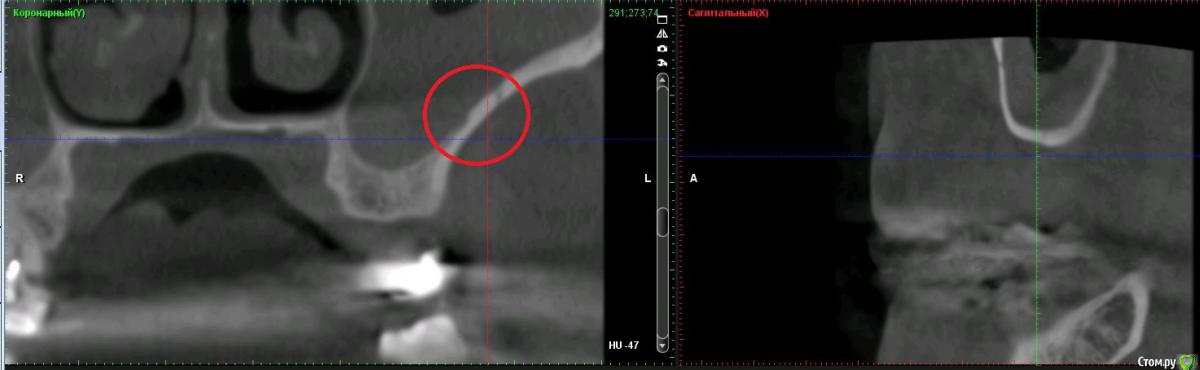

Дмитрий Л. Опубликовано 16 ноября, 2018 Автор Поделиться Опубликовано 16 ноября, 2018 (изменено) Bier, вы в целом согласны с планом идти отстрочено?Отметили, на сколько утолщена слизистая? Стучали бы по такой?) Irouil, предлагаете- перелечить 24, кальций 2-6 мес.- удалить 28- изготовить съёмник- выждать 4-6 мес. Повторить КТ, оценить гайморовую ?Или вы бы планировали синус в обл 26 тоже? Спасибо за комментарии. p.s. Это ведь сосуд? Изменено 16 ноября, 2018 пользователем Дмитрий Л. Ссылка на комментарий